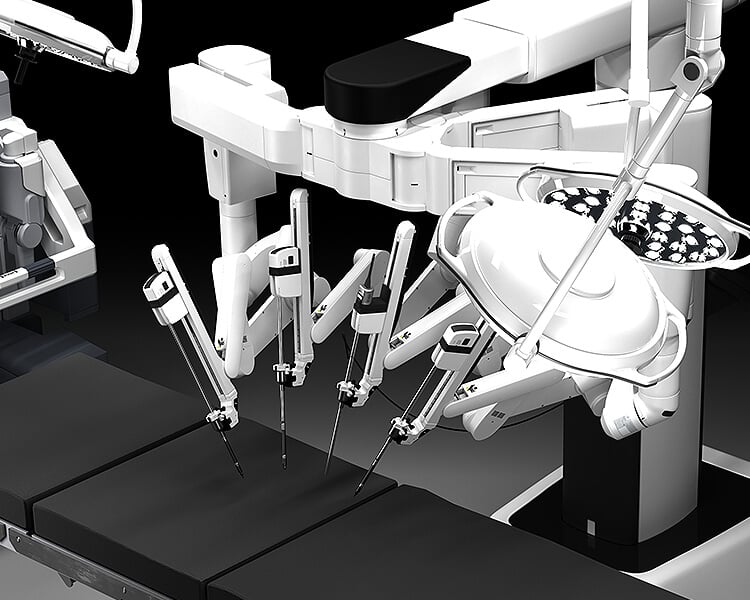

Founded in 1924, The Urology Group provides Northern Virginia and the Greater Washington area with the finest and most up-to-date urologic care available. Combining the most advanced techniques with a legacy of innovation in urologic care, The Urology Group treats over 14,000 patients per year.

The Urology Group of Virginia blends science, education and compassion to provide patients with award-winning urologic care with the personal touch of a community practice.